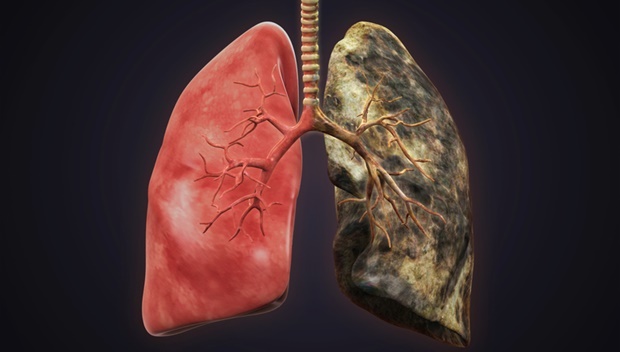

Οι πνεύμονες ενός καπνιστή

Οι υγιείς πνεύμονες έχουν ανοικτό ροζ χρώμα, ενώ οι πνεύμονες ενός καπνιστή έχουν σκούρο χρώμα και στίγματα οφείλονται στην εισπνεόμενη πίσσα από το τσιγάρο. Η υφή των δύο διαφέρει επίσης, με τον κατεστραμμένο πνεύμονα να είναι πολύ πιο σκληρός και “εύθραυστος” σε σχέση με τον υγιή.

Η Χρόνια Αποφρακτική Πνευμονοπάθεια (ΧΑΠ) είναι ένας τύπος αποφρακτικής πνευμονικής νόσου, στην οποία, μακροπρόθεσμα, η ροή του αέρα στους πνεύμονες είναι ανεπαρκής. Μοιάζει με το άσθμα που προκαλείται από το κάπνισμα, το οποίο μπορεί να προκαλέσει και ΧΑΠ. Στην επόμενη φωτογραφία βλέπετε σε πολύ κοντινό πλάνο το εσωτερικό ενός πνεύμονα που παρουσιάζει πολλαπλές κοιλότητες γεμάτες εναποθέσεις άνθρακα (μαύρες κηλίδες).